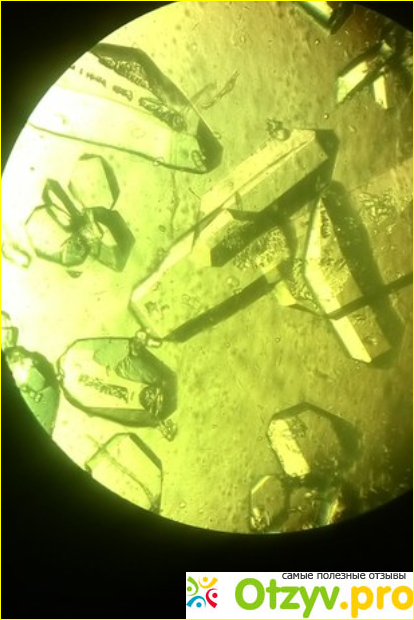

Хотелось бы начать с того что в принципе такое трипельфосфаты. Попросту говоря, на понятном языке, это кристаллы в кале. Их наличие определенной не говорит ни о чём хорошем. Во-первых у нормального здорового человека, Да в принципе будто человек или животное, в кале не должно быть никаких абсолютно кристаллов. То есть они должны полностью отсутствовать. Если же они всё-таки есть, то потребуется другие дополнительные анализы, для того чтобы установить причину их появления, а также определение вида кристаллов.Отзыв о Трипельфосфаты в кале

Трипельфосфаты, или как Я уже говорила кристаллы бывают разных видов. В первую очередь это может говорить о каких-то проблемах в толстой кишке. Это могут быть какие-то гнойные образования, или же что-то другое. Для того чтобы узнать что же всё-таки это может быть, и о каком заболевании или отклонении говорят трипельфосфаты, для этого нужно определить какой же категории они всё-таки относятся. Это помогает определить причину их образования. Есть один вид кристаллов, который в незначительном количестве всё-таки может присутствовать в кале. Но самое главное здесь обратить внимание чтобы этот показатель был в норме, То есть я хочу подчеркнуть что я действительно должна быть небольшое количество. Если же количество их превышено то скорее всего происходит какой-то воспалительный процесс. Опять-таки в толстой кишке. Также есть и другой вид кристаллов, который при наличии может говорить о том что у человека, И опять таки может быть у животного, есть какие-то кишечные паразиты. Такой вид кристаллов покажет об этом.Трипельфосфаты в кале фото1